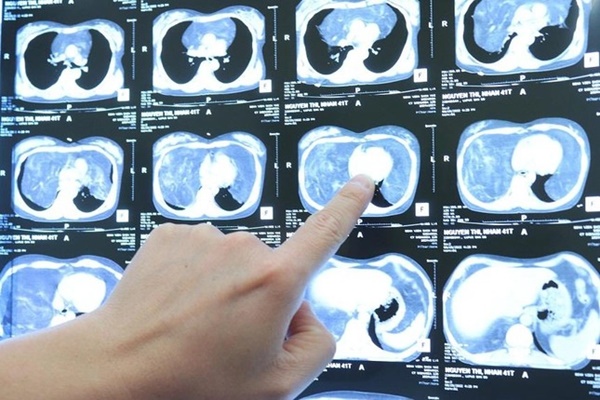

Chị Hoa bị bệnh Lupus (một loại bệnh lý gây ra do rối loạn đáp ứng miễn dịch) nhiều năm nay vẫn định kỳ đi khám và điều trị tại Bệnh viện Bạch Mai. Gần đây chị thấy đau tức ngực, khó thở nhiều, triệu chứng ngày càng nặng. Bác sỹ cho chụp cắt lớp thì phát hiện chị có u trung thất lớn, trọng lượng khoảng 4kg, chiếm phần lớn thể tích lồng ngực. Khối u lớn làm giảm thể tích trường phổi hai bên, gây chèn ép tim và các mạch máu lớn trên nền bệnh lý mãn tính gây không ít lo ngại cho quá trình điều trị. Sau khi hội chẩn liên khoa Tim mạch, Dị ứng, Gây mê hồi sức, Phẫu thuật lồng ngực để tìm phương án, các bác sĩ đã quyết định phẫu thuật để cắt bỏ khối u.

ThS.BS. Ngô Gia Khánh, Trưởng Khoa Phẫu thuật lồng ngực mạch máu - Bệnh viện Bạch Mai, người trực tiếp phẫu thuật cho bệnh nhân Hoa cho biết: Khối u là tổ chức mỡ, chiếm toàn bộ trung thất và phần dưới khoang màng phổi, ranh giới u tương đối rõ với các tổ chức xung quanh. Với trọng lượng sau khi cắt khoảng 4kg, khối u khổng lồ khiến hai phổi của bệnh nhân bị đẩy lên trên, ôm quanh tim và các mạch máu lớn. Đây chính là nguyên nhân dẫn đến việc bệnh nhân Hoa bị tức ngực, khó thở. Chia sẻ về độ phức tạp của ca phẫu thuật, ThS.BS. Gia Khánh cho biết: Khối u to, đường mổ lớn nên nguy cơ mất máu, đau sau mổ rất lớn. Êkip gây mê và phẫu thuật đã phải phối hợp và theo dõi sát từng chỉ số huyết động trong mổ, phẫu tích, bảo tồn các cấu trúc mạch máu, thần kinh trong toàn bộ cuộc mổ để hạn chế mất máu mà vẫn lấy trọn khối u lớn, giải phóng hai phổi khỏi bị chèn ép.